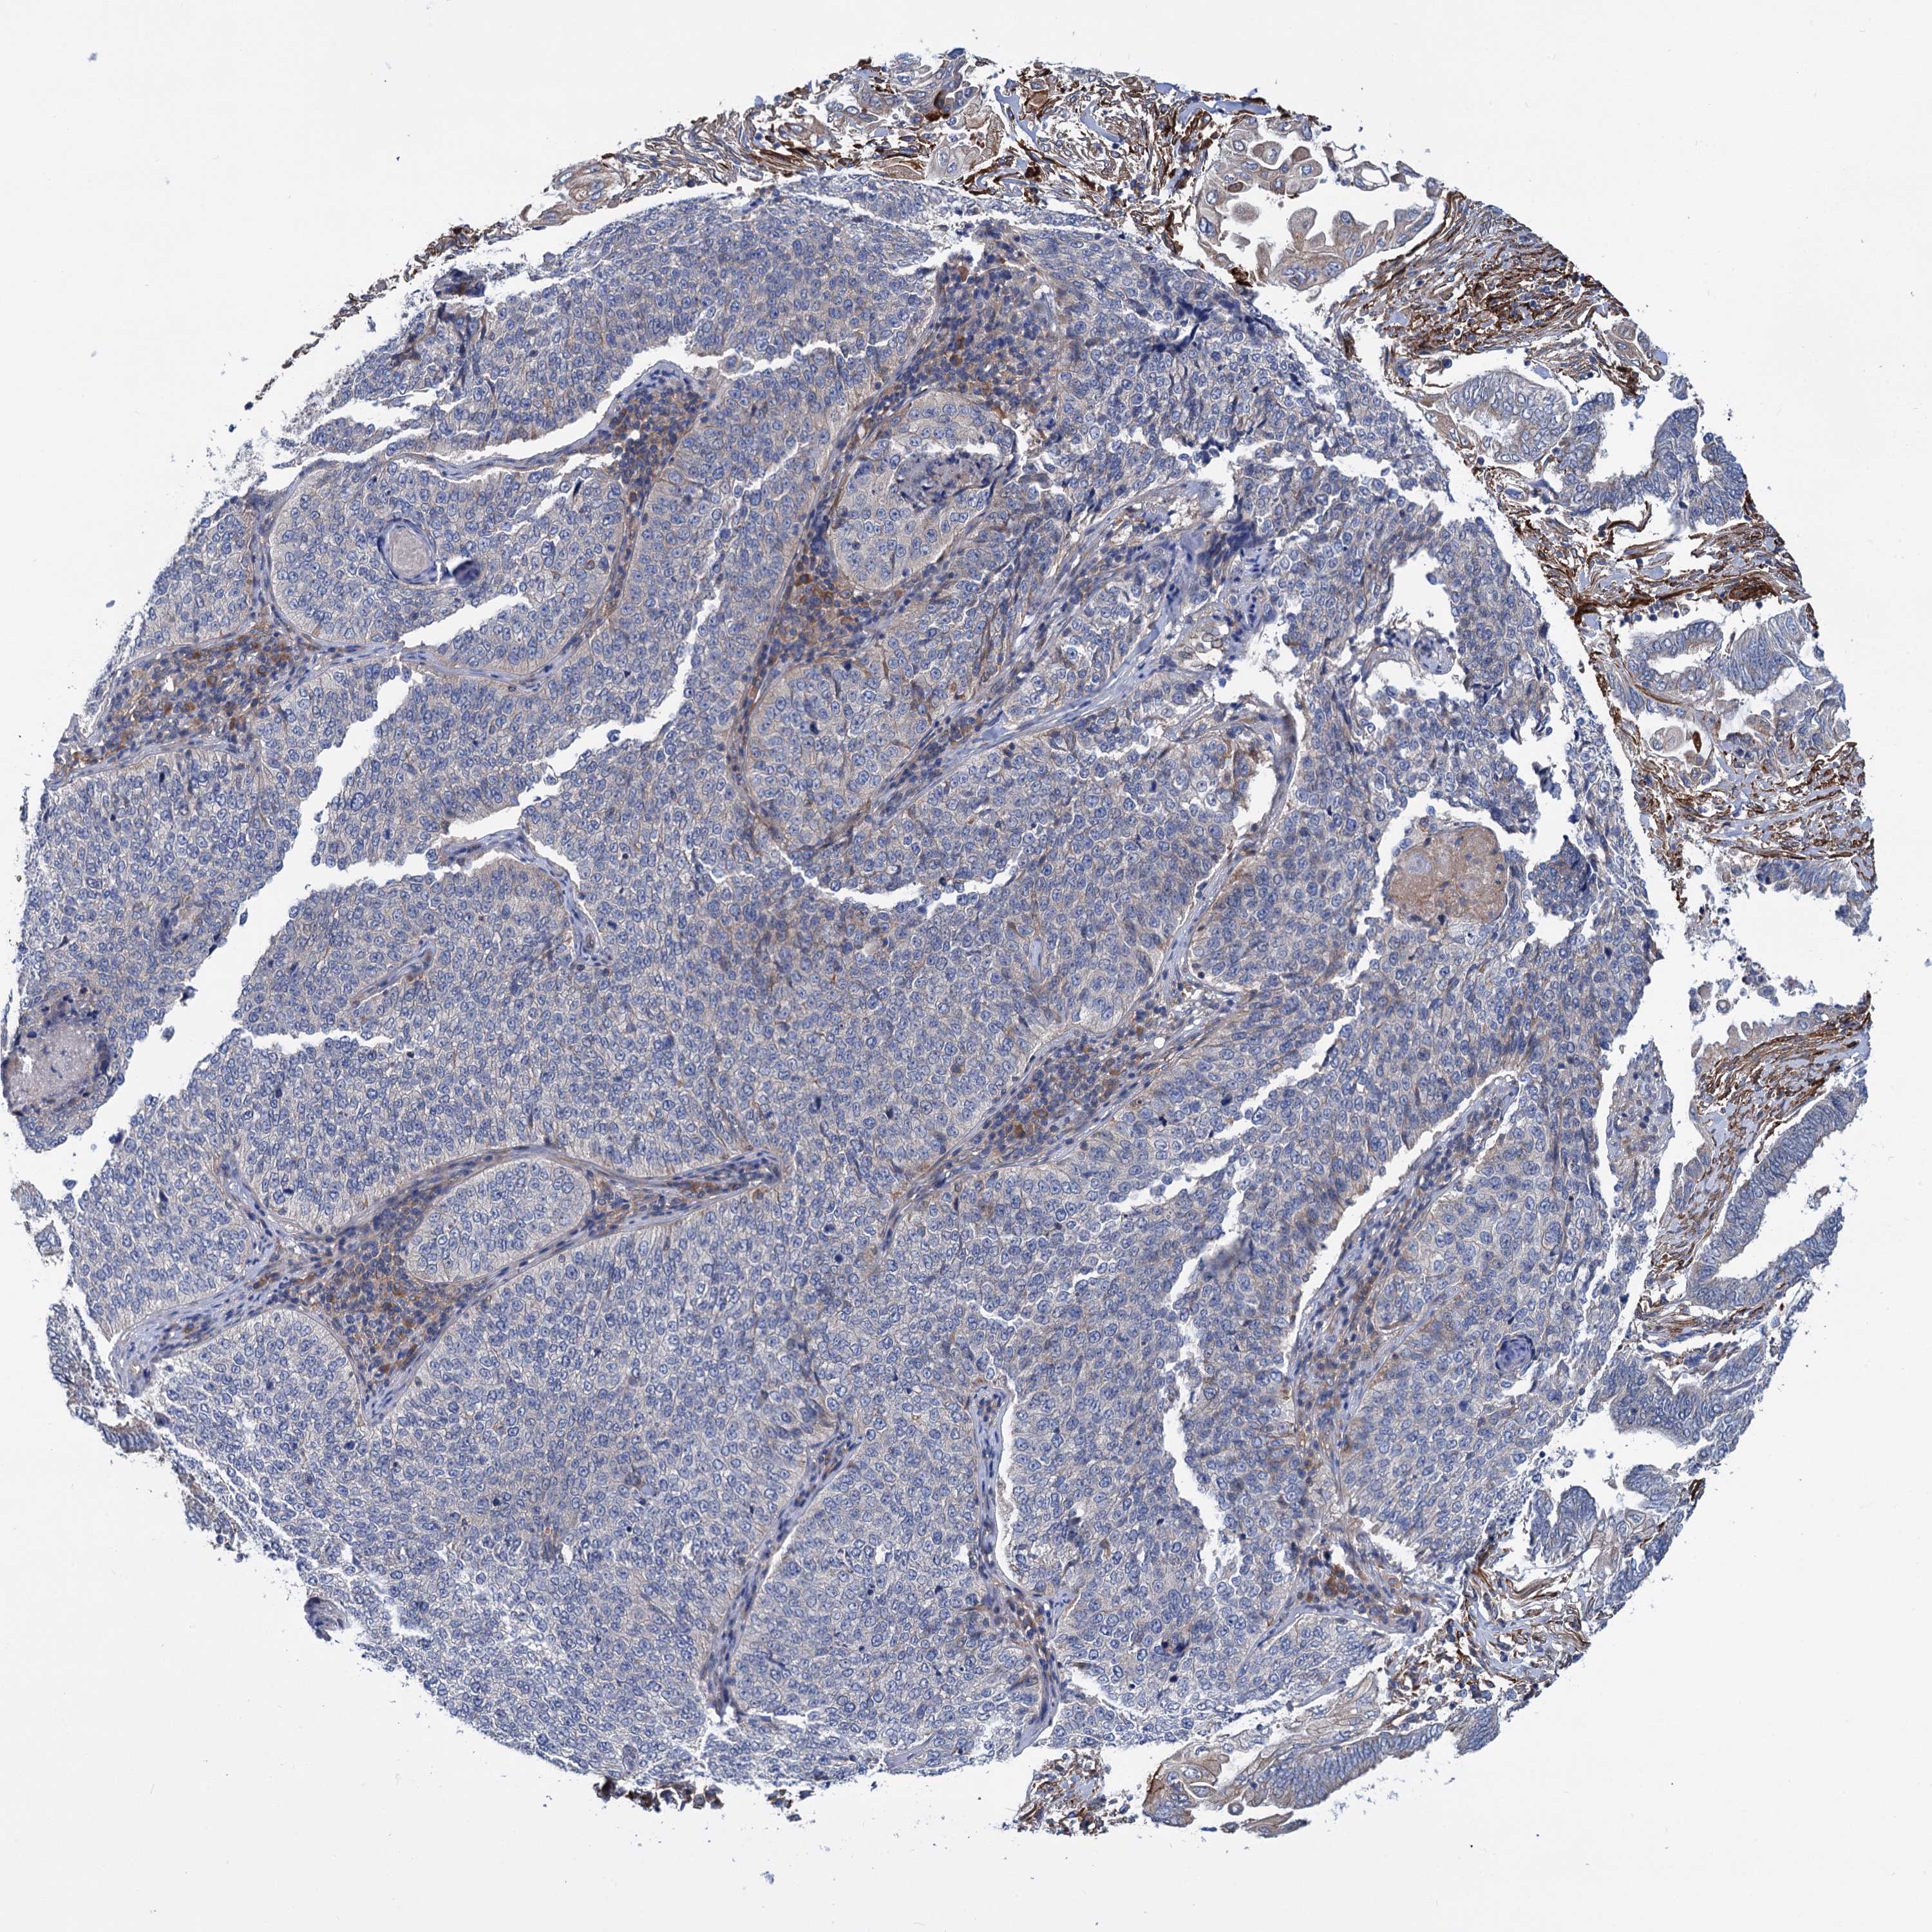

CERVICAL CANCER - Protein expressioni

A mouse-over function shows sample information and annotation data. Click on an image to view it in a full screen mode. Samples can be filtered based on level of antibody staining by selecting one or several of the following categories: high, medium, low and not detected. The assay and annotation is described here.

Note that samples used for immunohistochemistry by the Human Protein Atlas do not correspond to samples in the TCGA dataset.

Antibody stainingi

Antibody staining in the annotated cell types in the current human tissue is reported as not detected, low, medium, or high, based on conventional immunohistochemistry profiling in selected tissues. This score is based on the combination of the staining intensity and fraction of stained cells.

Each image is clickable and will lead to virtual microscopy that enables deeper exploration of all samples and also displays staining intensity scores, fraction scores and subcellular localization as well as patient and tissue information for each sample.

Antibody HPA038793

Antibody HPA053691

Staining

High

Medium

Low

Not detected

Intensity

Strong

Moderate

Weak

Negative

Quantity

>75%

75%-25%

<25%

None

Location

Nuclear

Cytoplasmic/membranous

Cytoplasmic/membranous,nuclear

Squamous cell carcinoma, NOS

Adenocarcinoma, NOS